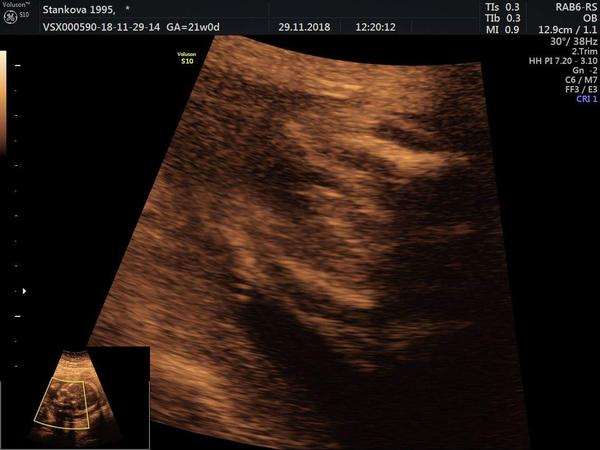

Hezký den, v 16tt řekli asi kluk ve 20tt žádného pindika neviděli můžu ještě doufat v holku? (foto v 16tt)

@tyna211 to, co tam vyčuhuje, bych tipla spíš na pupečník. Nám teď potvrdili kluka a vypadá to takto..

@hawah na vašem utz vidím kuličky i pindika na tom mém kuličky a na tom takové nějaké dvě čárky tak právě nevím no v úterý jdu na kardio tak uvidíme 🙂

Toto bylo v 21.tydnu a rekl nam, ze to bude kluk a opravdu kluka mame..... Takze je mozne, ze e to je kluk, a ze jde videdet jen pytlik